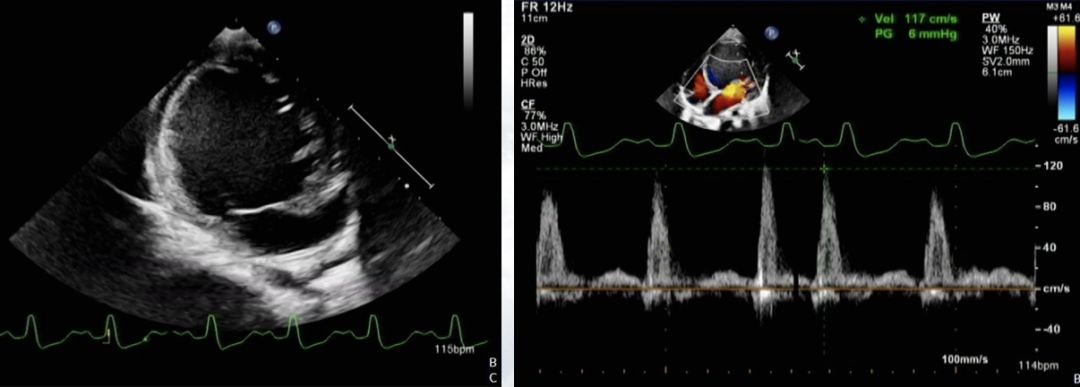

— 左室舒末内径:50mm,收末内径:43mm,EF 15%,E峰95cm/s,A峰 26cm/s

— 左室壁运动弥漫性减低,左室收缩功能减低,左心增大

✦ Case 2,幼儿,扩张型心肌病?HF、支原体感染、细小病毒B19感染、流感病毒B感染

— 减轻心脏负荷:① 呋塞米 2mg/kg bid;② 氢氯噻嗪 2mg/kg bid;③螺内酯 2mg/kg bid ;④液量负平衡:每日负100-300ml

— 改善微循环:5%NaHCO3 1-2ml/kg

— 正性肌力药:地高辛 0.5ml(25ug) qd